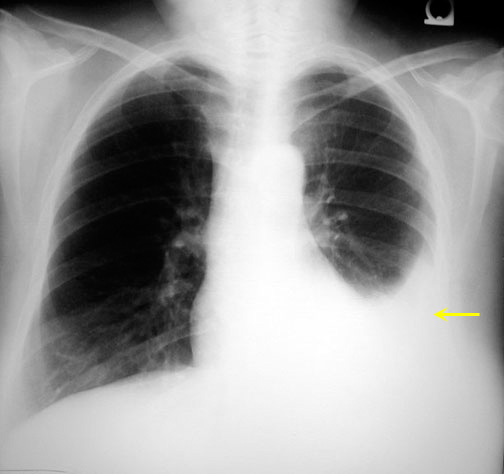

• Note pleural effusion on left (yellow arrow) in the adjacent CXR.

• Upper margin high in axilla in PA view (yellow arrows)

• Loss of silhouette. In the images below note lack of identifiable left diaphragm before and visible diaphragm after clearance of fluid (Silhouette sign principle)

Before  thoracentesis

Left diaphragm is not identifiable

After thoracentesis

Left diaphragm is seen clearly.